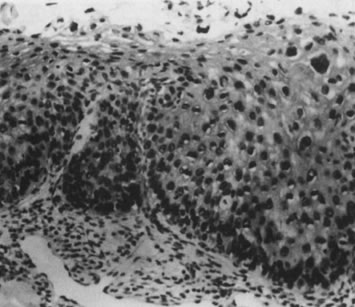

The surface may appear micropapillary (spiked), flat, or sometimes microconvoluted to a brainlike epithelial arrangement (Fig. 9). Many of the flat lesions have a pure, shiny-white color reminiscent of pearls, in contrast to the full, oyster-white color of high-grade cervical intraepithelial neoplasia (Figs. 10 and 11). Some HPV infections produce coarse capillary loops with a horizontal or vertical orientation, giving the appearance of a mosaic or punctation. The regular spacing of the vessels helps to differentiate these arrangements from invasive carcinomas.73,74 Histologically, the lesions contain koilocytotic and parakeratotic changes in the upper layers of the infected epithelium (Fig. 12).

Fig. 12. Cervical intraepithelial neoplasia grade 1. Nuclear atypia, increased mitoses, nuclear crowding, and occasional binucleated forms are seen on the parabasal cell layers. Koilocytotic changes are prominent in the upper cell layers. (Hematoxylin-eosin, ×500.)